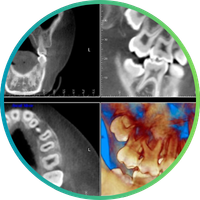

VENTA DE DISTINTOS EQUIPOS

Se venden equipos de imagenología dental (CBCT, pano/cefa, intraoral, digitalizadores) y también existe la opción de traspaso de centro(s) radiológico(s) en funcionamiento en la V Región.

• Equipos operativos

• Posibilidad de llegar y trabajar

• Venta por equipo o negocio completo

Para más información, comunicarse al WhatsApp:

+56985963818

+56993216301

VENTA DE EQUIPO RAYOS X 3 EN 1

Disponible equipo de rayos X 3 en 1 (tele-pano-CBCT) para venta, arriendo o alianzas comerciales.

Una excelente alternativa para clínicas que buscan ampliar o modernizar sus servicios de diagnóstico.

Gonzalo Rubio

‪+56 9 9742 0600‬